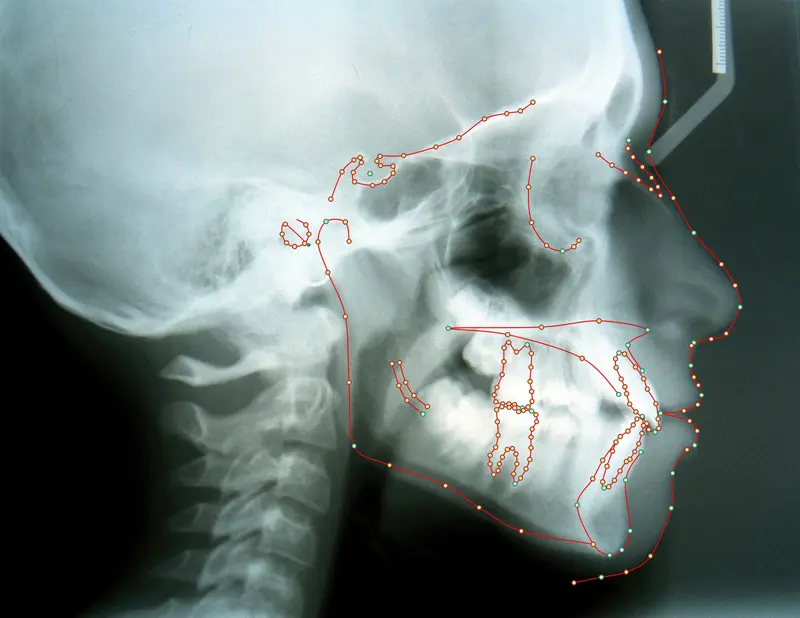

The Diagnosis

Bimaxillary protrusion (teeth flaring forward) causing lip incompetence. The patient struggled to close his lips comfortably, straining the chin muscle (mentalis).

The Engineering

A strategic extraction plan (4 premolars) allowed us to retract the front teeth. Note the dramatic improvement in chin projection and facial balance. The extractions did not flatten the face; they harmonized it.